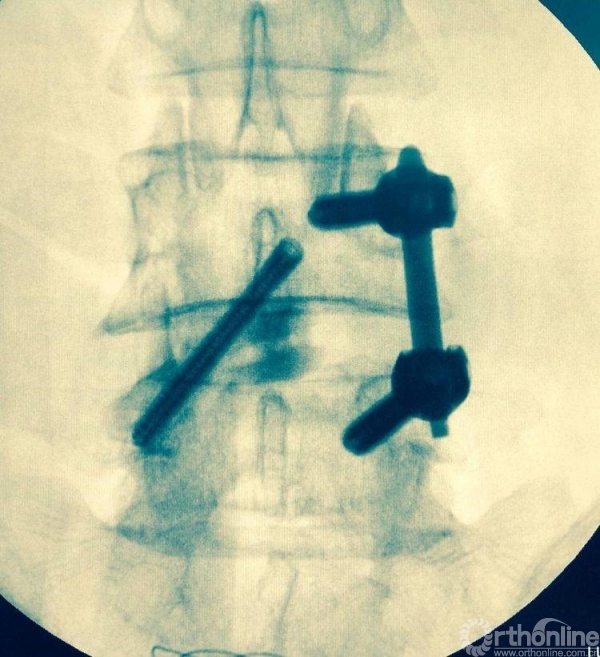

术后正、侧位片

植入钉棒位置较为合理

椎管狭窄减压较术前容积扩大

矢状位融合器、植骨位置及滑脱复位情况

术后三维CT资料